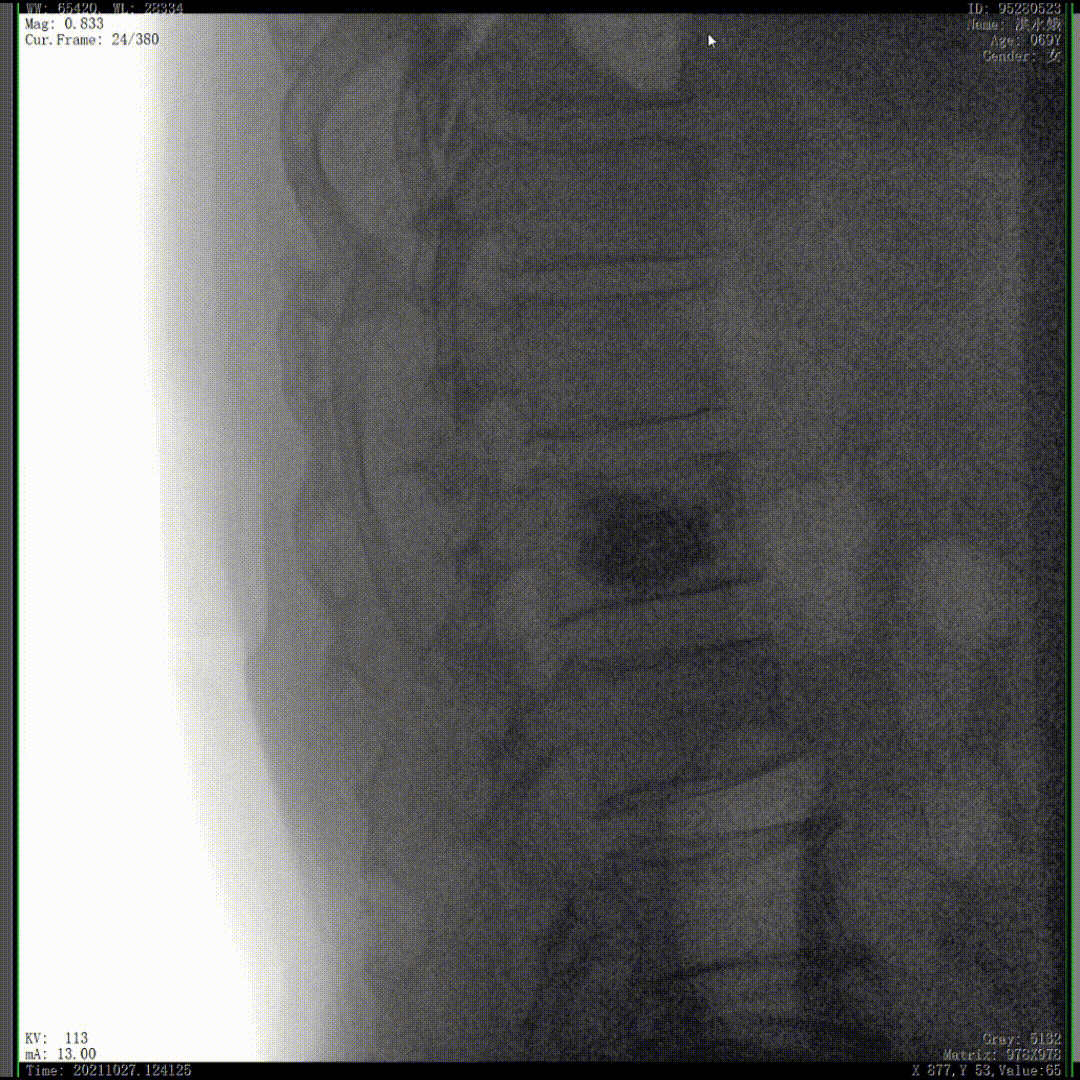

通常上頸椎的手術(shù)是非常復(fù)雜的,因?yàn)獒t(yī)生要把釘子打在上頸椎這樣一個(gè)很狹小的通道里面,周圍都是重要的神經(jīng)血管,一旦損傷到頸椎,就有可能造成病人的死亡。隨著醫(yī)學(xué)影像技術(shù)的不斷發(fā)展,在三維影像的引導(dǎo)下,整個(gè)打進(jìn)去的通路能夠完全的展現(xiàn)在我們的眼睛里,讓這種復(fù)雜的手術(shù)變得簡(jiǎn)單了,更多的醫(yī)生就可以去開展這樣的手術(shù)了,也會(huì)有越來越多的病人從中獲益。

我們完成了椎體成形術(shù)以后,在二維的正側(cè)位影像上還不能看清骨水泥的滲漏情況,通過三維影像就可以360°的觀察骨水泥在椎體里到底是怎么彌散的。如果當(dāng)時(shí)我們判斷出來質(zhì)量不好,可能還需要進(jìn)行翻修,這是在二維影像上不能看到的。